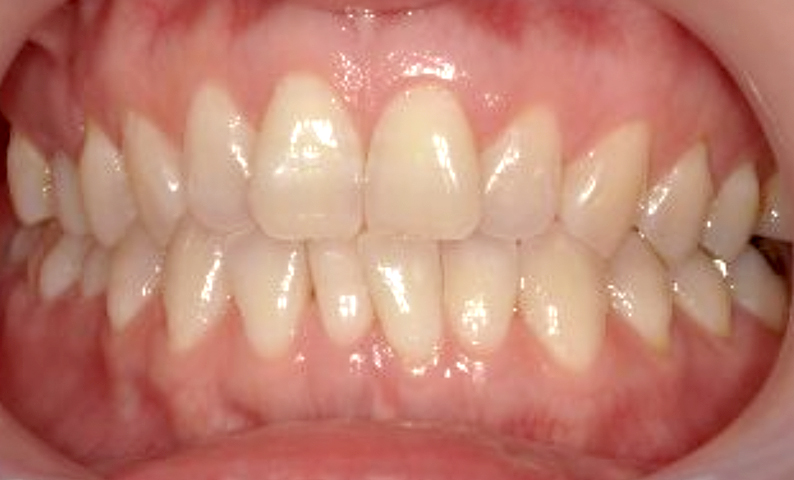

症例_030 上下顎の部分矯正

治療期間:12ヶ月金額:54万円+税女性八の字/V字型捻転歯前歯のガタガタ